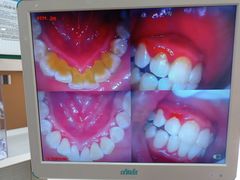

• 圣贝口腔(海淀店)

• -圣贝口腔(海淀店)